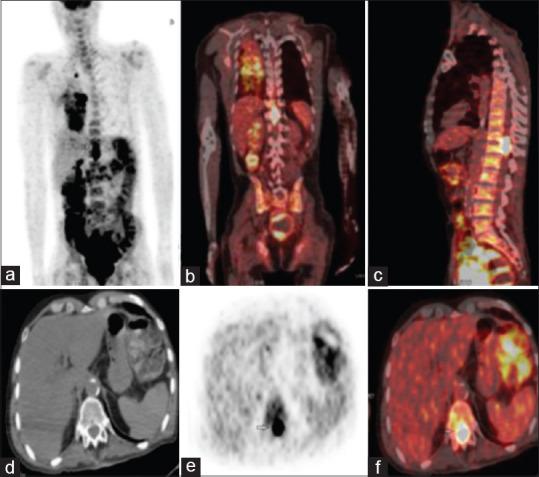

Intramedullary spinal cord metastases (SCMs) are extremely rare. Here, we report a case of a 60-year-old man with a history of right nonsmall cell lung cancer treated by concomitant radiochemotherapy who complained, 9 months after treatment completion, of chest pain, breath shortness, and more recently back pain. An F-FDG PET/CT was performed as part of the restaging process and showed a hypermetabolic mass of the right lung in addition to ipsilateral mediastinal hypermetabolic lymph nodes. There was also an FDG avid lesion of thoracic spinal cord at the T11-T12 level consistent with SCM as confirmed by MRI.

脊髓髓内转移瘤(SCMs)极为罕见。在此,我们报告一例60岁男性病例,该患者有右非小细胞肺癌病史,接受过同步放化疗,在治疗结束9个月后,出现胸痛、气短,近期还出现背痛。作为再分期检查的一部分,进行了F-FDG PET/CT检查,结果显示右肺有一个高代谢肿块,同侧纵隔也有高代谢淋巴结。此外,MRI证实,在T11-T12水平的胸段脊髓有一个FDG摄取增加的病灶,符合脊髓髓内转移瘤。